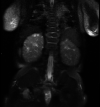

Figure 3. Axial and coronal T1-weighted (A and C) and T2-weighted (B and D) magnetic resonance images of the abdomen.

The images demonstrate a large right hemiabdomen hypointense T1/hyperintense T2 mass, compatible with a simple cyst. At the inferior margin of the cyst, the mass was seen to be connected with another cyst, which was felt to be possibly due to an ovarian origin (arrow; D). Significant mass effect on the inferior liver as well as displacement of the bowel loops to the left is noted.

Figure 4. Coronal T2-weighted image of the abdomen.

The image demonstrates heterogeneous, dysplastic-appearing kidneys bilaterally with numerous scattered cysts in the renal parenchyma.